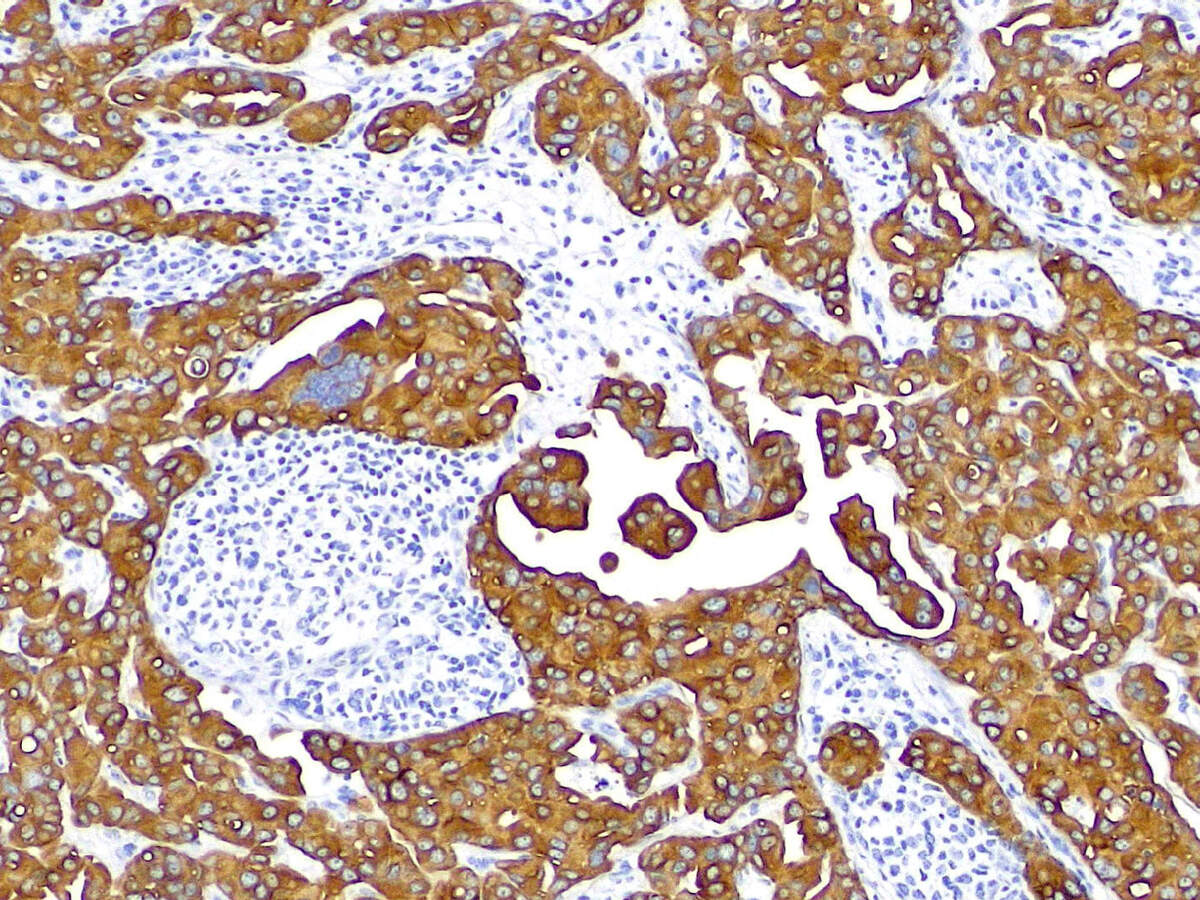

明场观察方式在多个学科领域都发挥着不可或缺的作用。在生物学领域,它常被用于研究细胞、组织、细菌等生物样本的微观结构和功能。在医学领域,明场观察则是病理学检查、临床实验室检测和血液分析等工作的重要辅助手段,为医生提供了宝贵的诊断依据。此外,在材料科学、环境科学等领域,明场观察同样发挥着重要作用,有助于研究人员深入了解材料的微观结构和性质。

应用领域:常规镜检、病理、染色标本